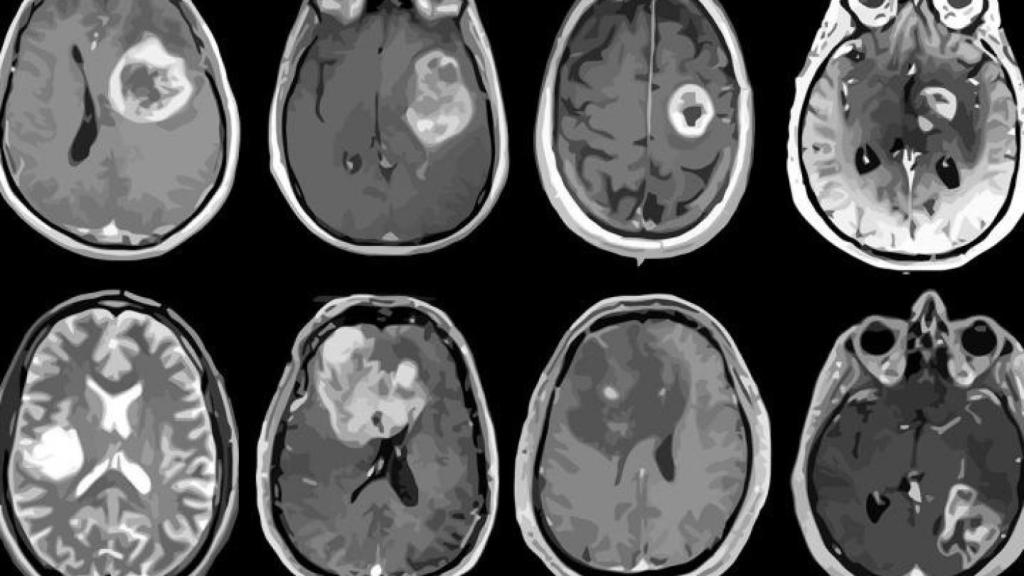

Mapa al detalle del glioblastoma, el tumor cerebral más común.

Los investigadores predoctorales de la Universidad de Valladolid (Uva) Elisa Moya y Rafael Navarro han conseguido generar, gracias a la inteligencia artificial, imágenes sintéticas que podrán utilizarse junto a las que se crean en una resonancia magnética, en el diagnóstico y la predicción del tratamiento del glioblastoma, el tipo más común de tumor cerebral maligno.

El glioblastoma es uno de los tumores cerebrales más agresivos, con un índice de supervivencia de aproximadamente un 40 por ciento en el primer año después del diagnóstico y un 17 por ciento en el segundo año, por lo que la predicción de su supervivencia resulta clave para el tratamiento eficiente y la planificación de la cirugía.

Esta nueva técnica desarrollada por los investigadores de la UVa, se suma a las que se utilizan actualmente en el diagnóstico, pronóstico y respuesta terapéutica a este cáncer cerebral, utilizando imágenes sintéticas de resonancia magnética y Radiómica. “Las imágenes sintéticas se generan con un sistema de inteligencia artificial que ha sido entrenado a partir de gran cantidad de imágenes reales obtenidas en las máquinas de resonancia magnética. Después utilizamos medidas matemáticas para comparar las imágenes sintéticas con las reales, usándolas también en la técnica de Radiómica, que se encarga de extraer características cuantitativas de las imágenes con las que lograr una herramienta predictiva para este tipo de cáncer cerebral. Esto puede facilitar una mejor planificación de su tratamiento o cirugía”, explicó Elisa Moya.